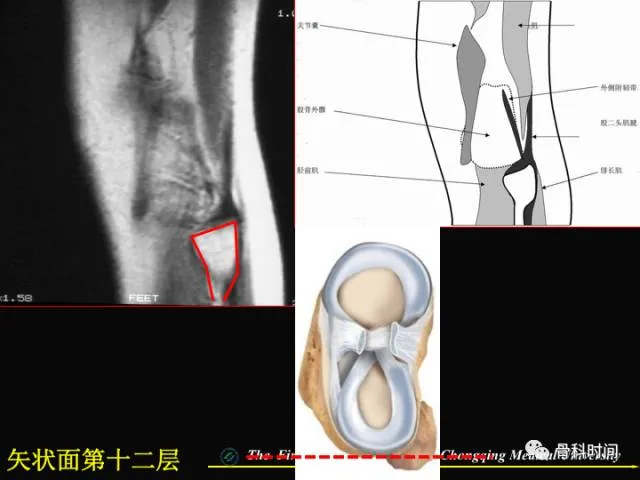

你知道半月板损伤的 MRI 是如何分级的吗?半月板撕裂的 MRI 表现又是怎么样的?

今天给大家分享一份精美 PPT,全方位详述膝关节半月板 MRI 的要点,一起来学习一下: